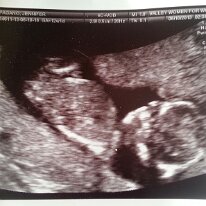

2013-06-10

6/10/13—2/16/19

June 10th

Our Baby